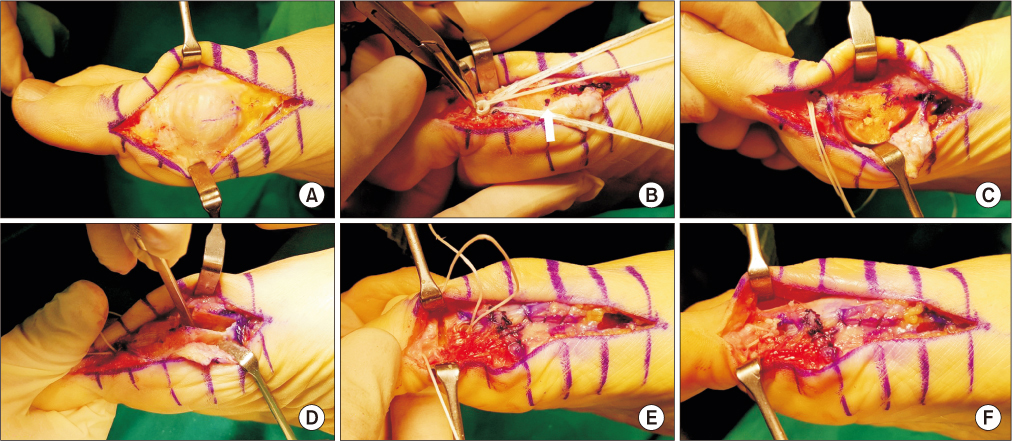

This study evaluated the clinical and radiological results after reinforcement of the weakened medial joint capsule using Internal Brace (Arthrex) for treating severe hallux valgus.

This study reviewed 56 cases of 50 patients that were followed-up postoperatively for at least 12 months, from September 2017 until August 2018. An extended distal chevron osteotomy combined with a distal soft-tissue release was performed by a single surgeon to treat severe hallux valgus. Internal Brace was applied in 12 cases (group A) who had weakened medial joint capsules, and capsulorrhaphy was performed in 44 cases (group B), and these two groups were compared postoperatively for the clinical and radiological results. The postoperative complications were also investigated.

Based on these results, we recommend the capsule reinforcing technique using Internal Brace as a successful operative option for treating a weakened medial capsule in patients with severe hallux valgus.